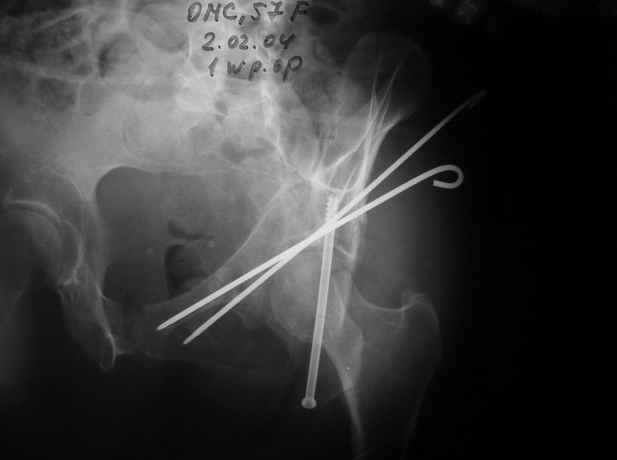

Anatoly F Lazarev 03 Сентябрь 2004, 22:18

Женя! Класный перелом. Отлично репонируется изнутри таза, но лучше фиксированть сзади. Классический перелом для двустороннего доступа.

Однако есть альтернатива. Репозиция из подвздошного доступа тазовыми щипцами с разнодлинными браншами или тазовым пистолетом, а фиксация задней колонны через седалищный бугор или тазрвыми винтами 4,5 или каннюлированными 6,5 или 7,3. По-моему я посылал на ортофорум такой снимок, когда жаловался на ишемический неврит седалищного нерва через сутки после операции. Не забудь про шейку бедра - мне кажется будет хорош длинный PFN любой фирмы, какую ты найдешь, а нет так UFN + miss a nail, как это здорово делают мои земляки - Ебурбуки. Пока.

27.01.04

02.02.04